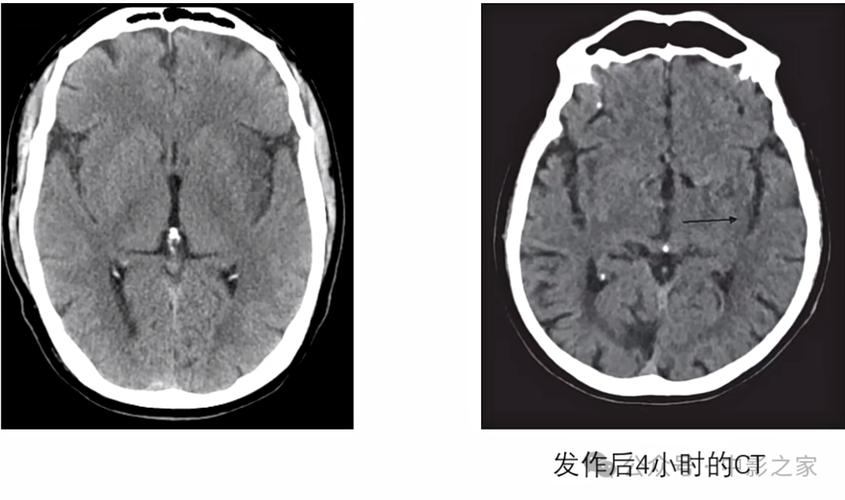

(图片来源网络,侵删)

- 抗血小板药物: 这是预防脑梗复发最核心的药物,它们能让血小板不那么“粘”,防止血栓再次形成,常用药物有:

- 他汀类药物: 这不仅仅是降血脂药,更是“血管的稳定剂”,它们能降低胆固醇、稳定斑块、抗炎,是预防脑梗复发的基石,常用药物有阿托伐他汀、瑞舒伐他汀等。